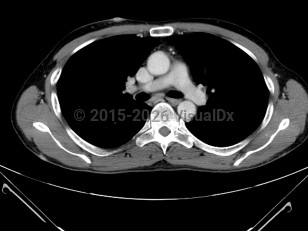

- Pulmonary – Can present with chest pain, shortness of breath, hemoptysis, or an incidental finding on chest X-ray.

PEL involves serosal surfaces of the body cavities, which include the pleura (60%-90%), pericardium (30%), peritoneum (30%-60%), and joint spaces. Thus it is also known as body cavity lymphoma. Clinical manifestations depend on the extent of serous effusions within those closed serosal surfaces, but there is no lymphomatous mass formation within those cavities. Patients usually present with dyspnea, chest pressure (secondary to pleural or pericardial effusion), abdominal distension and discomfort (due to ascites), or joint swelling.